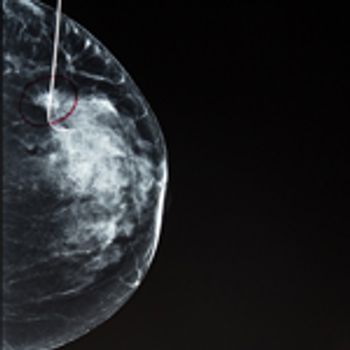

A 46-year-old woman had a routine screening mammogram that showed new calcifications in the posterior left breast. A diagnostic mammogram showed several small punctate calcifications, and a 6-month interval follow-up was recommended.